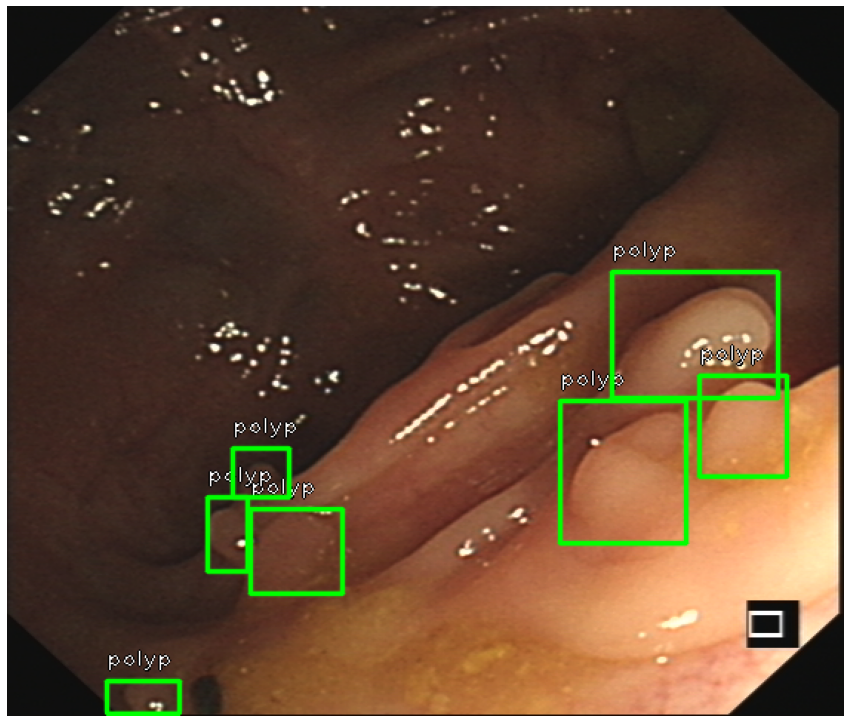

General objects for detection task such as car, pedestrian or table which have defined outline or appearance which offers strong cues for neural network to learn. Polyps, on the other hand, have various sizes which scales from diminutive(<5mmabsent5𝑚𝑚<5mm) to giant(>30mmabsent30𝑚𝑚>30mm) Shussman2014 and present different appearances such as sessile or pedunculated,1. This makes detecting polyps using a general-purpose oriented network more difficult and urges us to design a object-specific detector.

Refer to caption

(a) sessile

(b) pedunculated

(c) multiple objects

Figure 1: Examples of possible polyp category within a frame: (a) sessile, (b) pedunculated or (c) multiple of them.